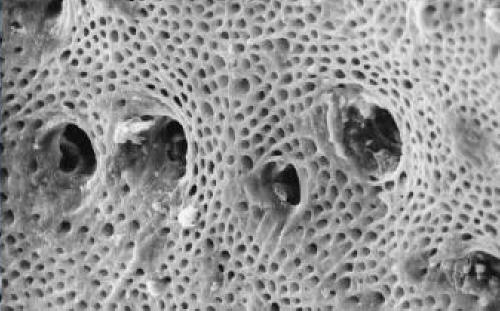

La dentina es un tejido conectivo mineralizado

con una matriz orgánica de proteínas colágenas.

La dentina tiene canales microscópicos, llamados

túbulos dentinarios, que se irradian hacia

afuera a través de la dentina desde la cavidad

pulpar hasta el borde exterior del cemento o del

esmalte. [15] El diámetro de estos túbulos varía

de 2.5 μm cerca de la pulpa, a 1.2 μm en la

porción media, y 900 nm cerca de la unión

dentino-esmalte. [16] Aunque pueden tener

pequeñas ramas laterales, los túbulos no se

cruzan entre sí. Su longitud está dictada por el

radio del diente. La configuración

tridimensional de los túbulos dentinarios está

determinada genéticamente.